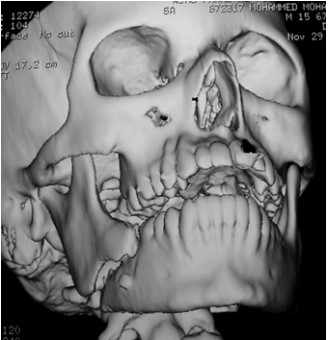

Fig 3: Panoramic radiograph of angle fracture associated with third molar.

The medical records and panoramic radiographs, C.T and 3D C.T (figures 1-4) of 50 patients with mandibular angle fractures were examined. The presence and absence and degree of impaction of the lower third molar were assessed for each patient and related to the occurrence of fracture of the mandibular angle in addition to evaluate the degree of displacement of the fracture.

The incidence of mandibular angle fracture was found to be greater when a lower third molar was present. Patients exhibiting angle fractures associated with third molar represented 74 % of all angle fractures in this investigation.

In this study, mandibular angle fracture associated with lower third molar represented 74 % of all cases and this result provided an evidence that third molar tooth represents a weak point of the mandible that lowers the resistance of the bone to fracture. This result is in agreement with the result of researches of Lee et al ,Ugboko et al ,Joyce et al, Kim and Linda et al (10-14) .